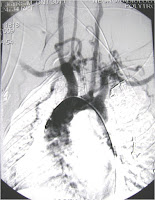

DSA: 2nd March 2009:

The aarch aortogram revealed a bunch of tortuous vessels aat root of neck bilaterally as well as amidline tortuous vessel (the anterior spinal artery) with an aneurysm. But what was surprising was that some of these vessels opened in the aorta lower down.

Suprised a thoracic aortogram was done which rrevealed a coarctation!